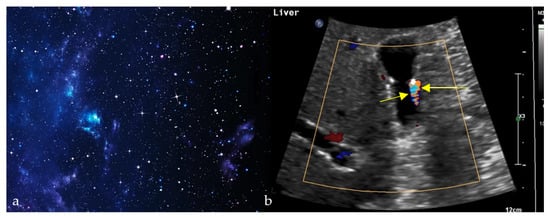

2.10. Twinkling Artifact